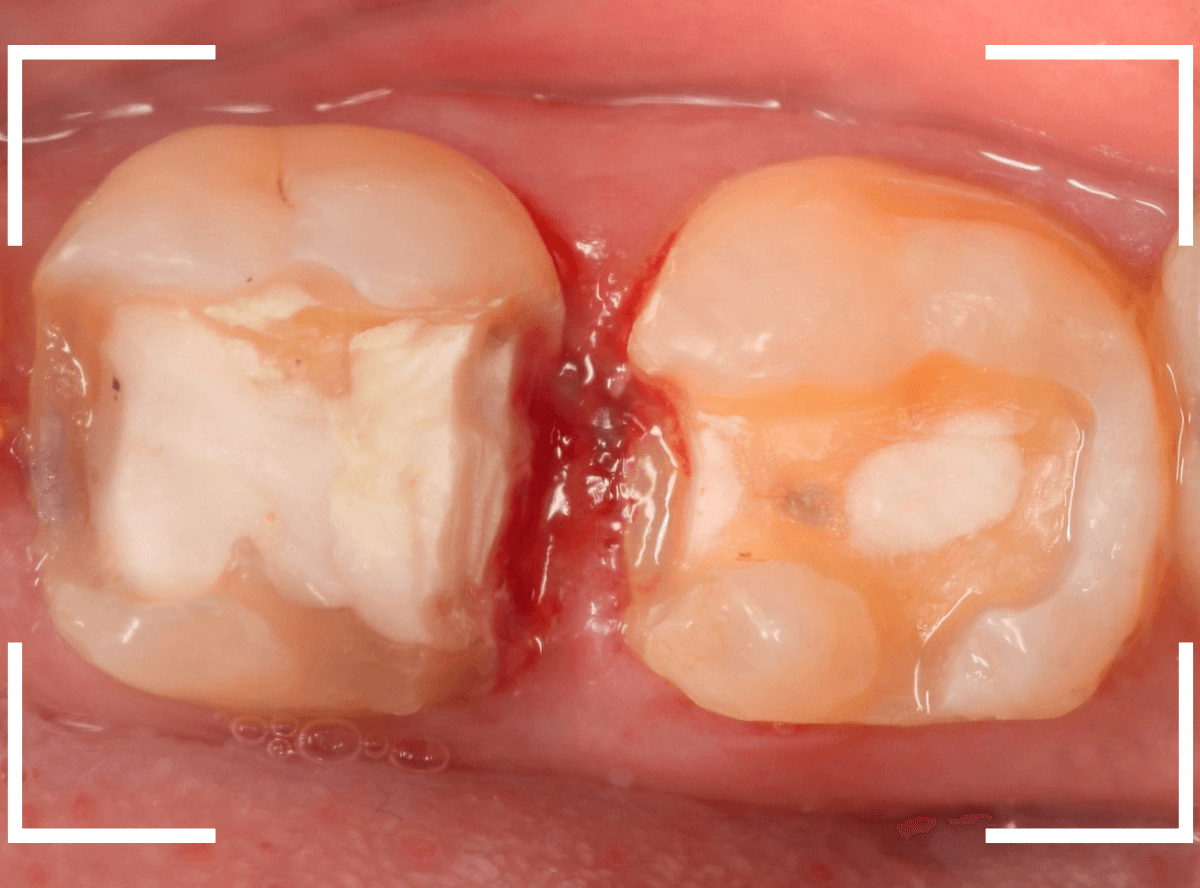

今回は、奥歯が神経に達する虫歯になってしまった患者さんのケースです。

隣りの歯とのすき間に大きな穴が空いているのが見えます。

レントゲン写真で確認します。

金属のつめものの下が、神経まで達する大きな虫歯になっています。

麻酔をして神経の治療をします。

さて、神経の治療が終わり、歯の土台を作ったところで、手前の歯の側面にも虫歯が見つかり、治療を始めました。

手前の歯の虫歯も金属の中まで虫歯になっていました。

手前の歯の虫歯もかなり広い虫歯でした。

ここで、両歯とも白い歯の治療を希望されましたので、E-MAXインレー、オールジルコニアクラウンで治療する事になりました。